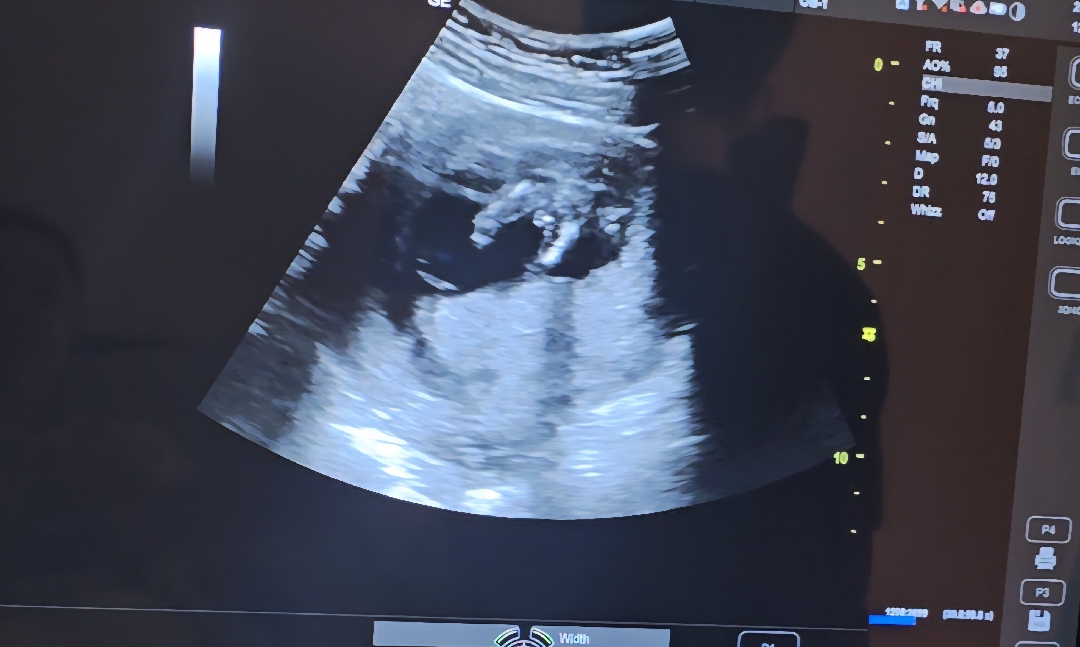

아들인가요???

아래에서 찍은건데 아들인가요

네아들이요ㅋ

아들같아요!